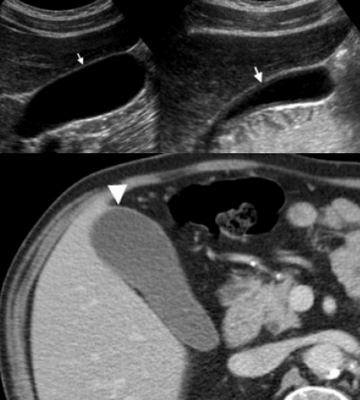

Слева — УЗИ — желчного пузыря у 59 летней женщины с острым холециститом. Субсерозный отек так, как гипоэхогенное утолщение между гиперэхогенными слоями (мышечным и слизистым). Справа — КТ брюшной полости с контрастным усилением. Также визуализируется субсерозный отек так, как наружный слой гиподенсный.

Острый калькулезный холецистит. После контрастного усиления визуализируется растянутый желчный пузырь (белые наконечники) со слегка утолщенной стенкой. Визуализируется камень в шейки желчного пузыря (белая стрелка).

Сверху изображения пациента 62 лет с калькулезным холециститом. На УЗИ визуализируется стенки желчного пузыря растянутые, с субсерозным отеком (указано белыми стрелками) и в просвете желчного пузыря камень и взвесь. На КТ визуализируется переход воспалительного процесса с желчного пузыря на соседние ткани (перихолецистит).